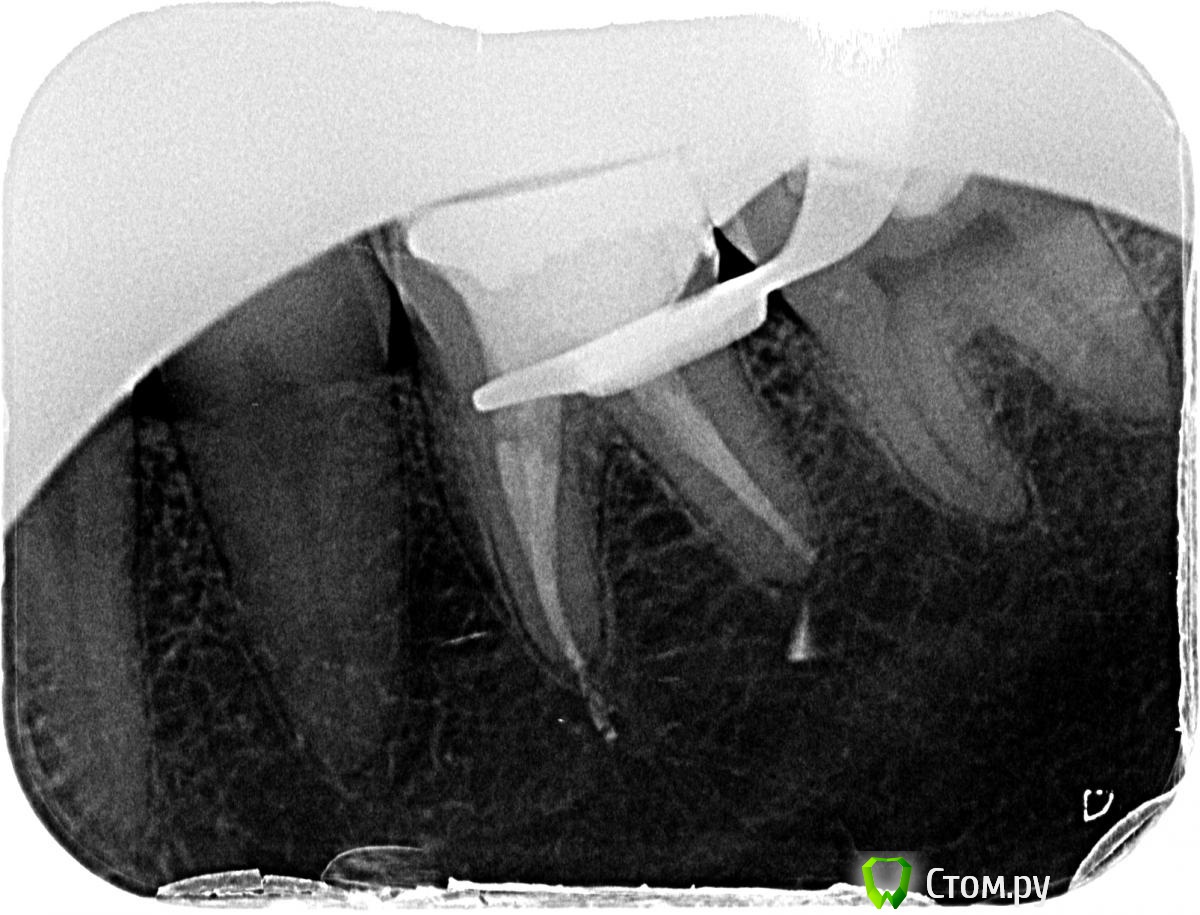

pacient7 Опубликовано 8 апреля, 2014 Поделиться Опубликовано 8 апреля, 2014 (изменено) Уважаемые доктора, помогите пожалуйста! Предыстория: полгода назад нащупал языком, что выпала пломба с левой стороны, боли не было. Пошел к стоматологу, тот осмотрел и сказал что ничего экстренного нет, обычный кариес. Во время осмотра был сделан рентген и доктор немного постучал по зубам. После визита к врачу появилась слабая ноющая делокализованная боль с левой стороны, и время от времения стали беспокоить короткие боли в области левого глаза (бровь, висок). Через две недели пришел к этому же врачу и он, с перерывом в неделю, поставил две пломбы на нижнюю левую шестерку и верхнюю левую семерку. Эндодонтического лечения не делал, сказал что не надо. После этого боли усилились, и в области глаза (в области левого глаза, бровь, висок, + давление в ушах) и иногда в области пролеченных зубов. Затем я был также на приеме у двух разных ЛОРов, сделал МРТ головы, и на МРТ все в норме. Оба ЛОРа сказали, что по поводу ЛОР все в порядке, и предположили, что это челюстной сустав дает боль. Затем я был у челюстного ортопеда (у двух). Один челюстной ортопед сказал, что это может быть "TMJ syndrom" (челюстная связка)", а может быть надо удалять левую верхнюю восьмерку. Второй челюсной ортопед сказал что признаков TMJ синдрома нету, и надо идти к стоматологу долечивать зубы. Я ждал несколько недель, думал что должно пройти само. Не прошло. Пришел на прием к другому стоматологу (дипломированный эндодонтолог, с навороченным эндодонтическим микроскопом итд). Тот покритиковал предыдущего стоматолога, перелечил за большие деньги нижнюю шестерку (пролечил три канала, поставил сверху большую пломбу, и сказал, что потом потребуется коронка). Это лечение не помогло решить проблему с болью в глазу. Я ждал месяц чтобы убедиться что боли не остаточные после лечения, и снова пришел к эндодонтологу на прием. Он сказал, что надо попробовать удалить верхнюю левую восьмерку (зуб мудрости). Удалил. Было дико больно около недели, потом через три-четыре недели боль на месте раны утихла, но проблему с болью в голове это не решило. Потом я пришел на прием к независимому стоматологу, где мне систематически постучали по всем зубам, поприкладывали лед, и покололи острым пинцетом десна (тест на парадонтоз). В результате все болезненные ощущения десен были около пролеченных зубов слева (и сверху и снизу). Тест на лед выявил, что у меня болезненные ощущения на нижней шестерке (эндодонтически леченной) и нижней семерке (не леченой). Я пришел к эндодонту с этими результатами, он предложил на выбор (1) удалить верхнюю левую семерку (или перелечить ее за астрономическую сумму, потому что первый стоматолог, оказывается, замазал каналы но не заполнил их), или (2) сделать эндодонтическое лечение нижней левой семерки, на которой он нашел глубокий узкий кариес. Я отказался от удаления семерки (так все зубы переудалять можно), и согласился на эндодонтическое лечение нижней шестерки. Лечили нижнюю семерку в два этапа: сначала, примерно месяц назад, ее вскрыли, прочистили и поставили временную пломбу. После этого все боли прошли! Голова абсолютно перестала беспокоить, и я пару недель чувствовал себя как нормальный человек. Затем, неделю назад я пришел на прием к этому доктору, тот закончил эндодонтическое лечение нижней семерки, поставил постоянную пломбу, и как только я вышел из его кабинета, я понял, что боль вернулась! Не только боль в только что леченном зубе, но и старая знакомая боль в голове (область глаза, висок, заложенность ушей). Сегодня: Беспокоит голова, абсолютно не могу работать. Кроме этого, болит при нажатии пальцем нижняя левая шестерка (которую эндодонтически лечили три месяца назад). Кроме этого, языком я нащупываю открытую десну между нижней левой шестеркой и семеркой (оба зуба эндодонтически леченные), и при надавливании языком на эту часть десны я ощущаю боль, которая коррелирует с болью в глазу. Эндодонт утверждает, что боль зуба при надавливании после трех месяцев лечения - это нормально. Так ли это? И он не горит желанием переделывать каналы, потому что это опять таки астрономическая сумма. Очень прошу помочь разобраться что происходит, и как и где лечить, Я прикрепил снимки которые есть. Отсутствует снимок после последнего лечения, я его завтра постараюсь достать. Очень буду благодарен за помошь! Изменено 8 апреля, 2014 пользователем pacient7 Ссылка на комментарий

pacient7 Опубликовано 10 апреля, 2014 Автор Поделиться Опубликовано 10 апреля, 2014 (изменено) Десна ТАК болеть не может. Сделайте тогда хотя бы актуальную ОПТГ-мы посмотрим, как 36, 37, 27 выглядят сейчас. И сустав заодно.Актуальная картинка нижней шестерки есть в моем первом посте. Актуальная каритинка нижней семерки есть у меня на компьютере, но я не могу ее загрузить, Форум ругается что превышен суммарный разрешенный размер файлов. Можно ли как-то удалить картинки которые были в первом моем посте? Изменено 10 апреля, 2014 пользователем pacient7 Ссылка на комментарий

pacient7 Опубликовано 10 апреля, 2014 Автор Поделиться Опубликовано 10 апреля, 2014 (изменено) Все-таки, хотелось бы услышать по поводу нижней шестерки (актуальный снимок после эндоднтического лечения прикреплен в первом посте). Надо ли ее вскрывать, если после трех месяцев после окончания эндодонтического лечения по-прежнему ощущаю боль при нажатии на зуб? Изменено 10 апреля, 2014 пользователем pacient7 Ссылка на комментарий

pacient7 Опубликовано 11 апреля, 2014 Автор Поделиться Опубликовано 11 апреля, 2014 Я прикрепил последний снимок, на котором видны нижняя левая шестерка и семерка.А панорамный точно нужен, или лучше сделать детальный снимок верхней семерки? Ссылка на комментарий

Korel Опубликовано 11 апреля, 2014 Поделиться Опубликовано 11 апреля, 2014 (изменено) А панорамный точно нужен? Понимаете, я сам не знаю ТОЧНО, что Вам нужно. Пока могу только предполагать (предположение изложил Выше , как и совет).На представленном последнем снимки есть кое какие проблемы, НО, опять же: думаю они не связаны с причиной.Поэтому ОПТГ не повредит точно, даже если и не поможет найти истинную причину Ваших болей, то понадобится позже , когда будет поставлен диагноз, начнётся осн. лечение и по ней (ОПТГ) Вы со спокойной душой будете решать проблемки, связанные с зубами. Изменено 11 апреля, 2014 пользователем Korel Ссылка на комментарий

pacient7 Опубликовано 11 апреля, 2014 Автор Поделиться Опубликовано 11 апреля, 2014 На представленном последнем снимки есть кое какие проблемыА какие конкретно есть проблемы с нижней шестеркой и семеркой на снимке? Семерка до сих пор реагирует на холодный сок (10 дней прошло после лечения). Шестерка до сих пор болит при нажатии (боьше чем три месяца прошло после лечения). Надо ли их перелечивать? Ссылка на комментарий

Korel Опубликовано 11 апреля, 2014 Поделиться Опубликовано 11 апреля, 2014 (изменено) http://s020.radikal.ru/i718/1404/9f/15f08af62cb2.jpg Это только для того, чтоб удовлетворить Ваше любопытство желание самому " решить" стоматологич. проблемы. Оно Вам надо? Не я один предлагал Вам обратиться к невропатологу (неврологу), почему бы не последовать советам? Перечитайте, пожалуйста свой первый пост. С чего всё началось? Изменено 11 апреля, 2014 пользователем Korel Ссылка на комментарий

pacient7 Опубликовано 11 апреля, 2014 Автор Поделиться Опубликовано 11 апреля, 2014 (изменено) Это только для того, чтоб удовлетворить Ваше любопытство желание самому " решить" стоматологич. проблемы.Не я один предлагал Вам обратиться к невропатологу (неврологу), почему бы не последовать советам?Перечитайте, пожалуйста свой первый пост. С чего всё началось? Началось все, мне кажется, с того, что меня попросили сильно сжать зубами какой-то стерженек, или пластинку во время рентгена. И каждый раз именно эта процедура (или аналогичная) вызывала появление боли. Стержень сжимался зубами с левой стороны в районе семерки или шестерки (сверху и снизу). Я теперь припоминаю, что последний раз тоже именно такой рентген был в конце, и мне после этого стало резко хуже. У одного невропатолога уже был, это ничего не дало. Записался еще к одному - запись на конец мая. Схожу конечно еще раз.А к эндодонтологу (который делал эти два зуба на последнем снимке) пойду на след. неделе. Задам ему Ваши вопросы по снимку. Все-таки выскажите пожалуйста Ваше мнение:1) Врачу который делал эти два зуба можно доверять третий зуб?2) То, что заливка выступает за пределы каналов это очень плохо? Это как-то можно/нужно исправлять?3) Зеленая стрелочка на снимке указывает на десну? С ней что-то не так? У меня там болит как раз. Языком нащупываю это место.4) Немного другой вопрос. Насколько важно в моем случае, чтобы у врача был эндодонтический микроскоп? Изменено 11 апреля, 2014 пользователем pacient7 Ссылка на комментарий